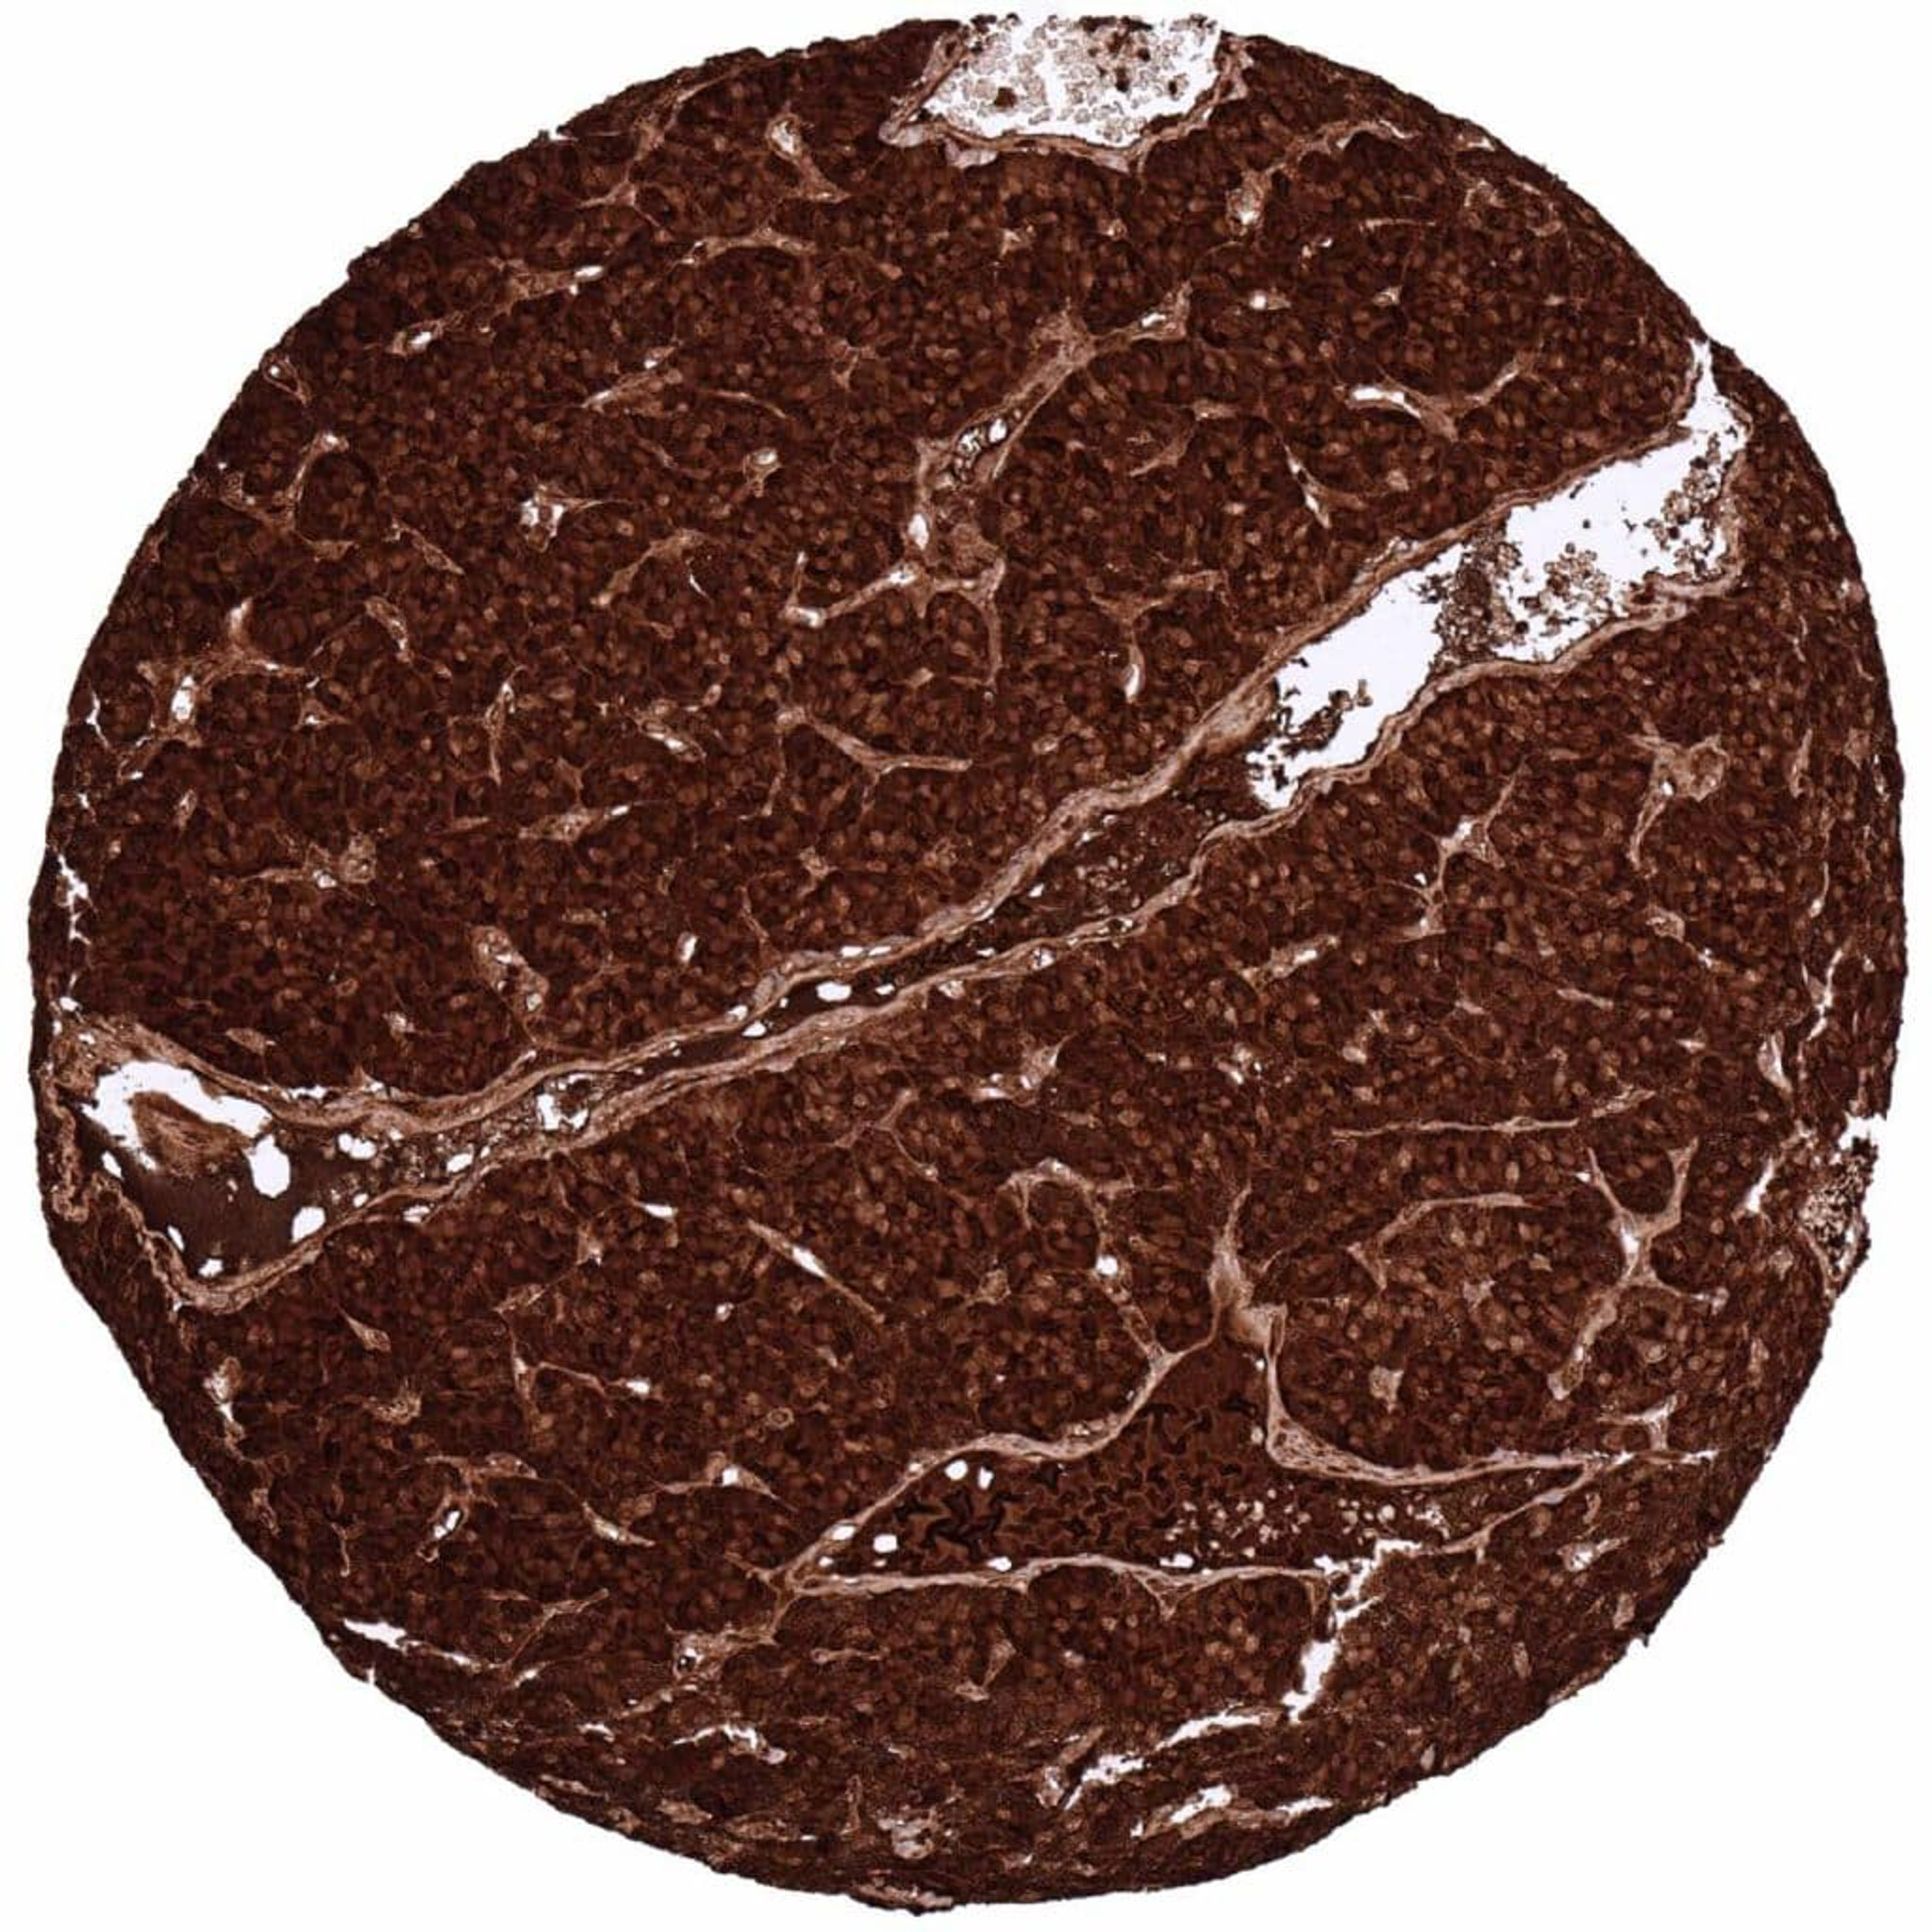

Pancreas – Neuroendocrine tumor with many intermingled C-peptide positive cells

Pancreas – Neuroendocrine tumor with numerous intermingled cells showing strong C-peptide staining